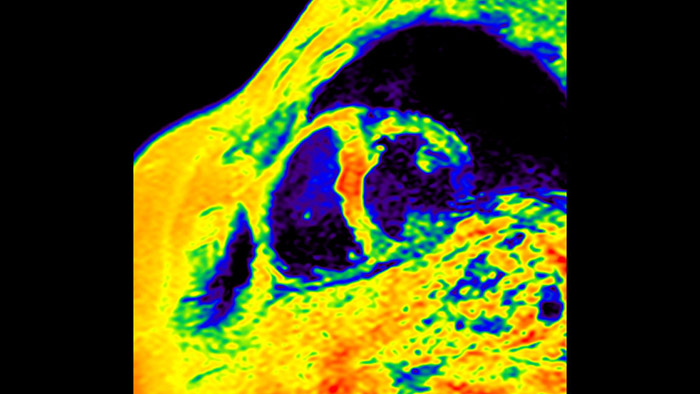

IntelliSpace Portal MR Caas5,6 Strain7 assists in patient diagnosis and monitoring by providing global strain parameters such as global longitudinal strain (GLS), global circumferential strain (GCS), and global radial strain (GRS), using short and long axis MR images, as well as describing the myocardium deformation- such as shortening, thickening, and lengthening during the cardiac cycle.

Today's diagnostics often cannot detect heart dysfunction until symptoms occur. MyoStrain utilises segmental strain to measure 48 segments of the heart and provides physicians with a unique diagnostic tool to help identify regional dysfunction before the heart as a whole is affected.